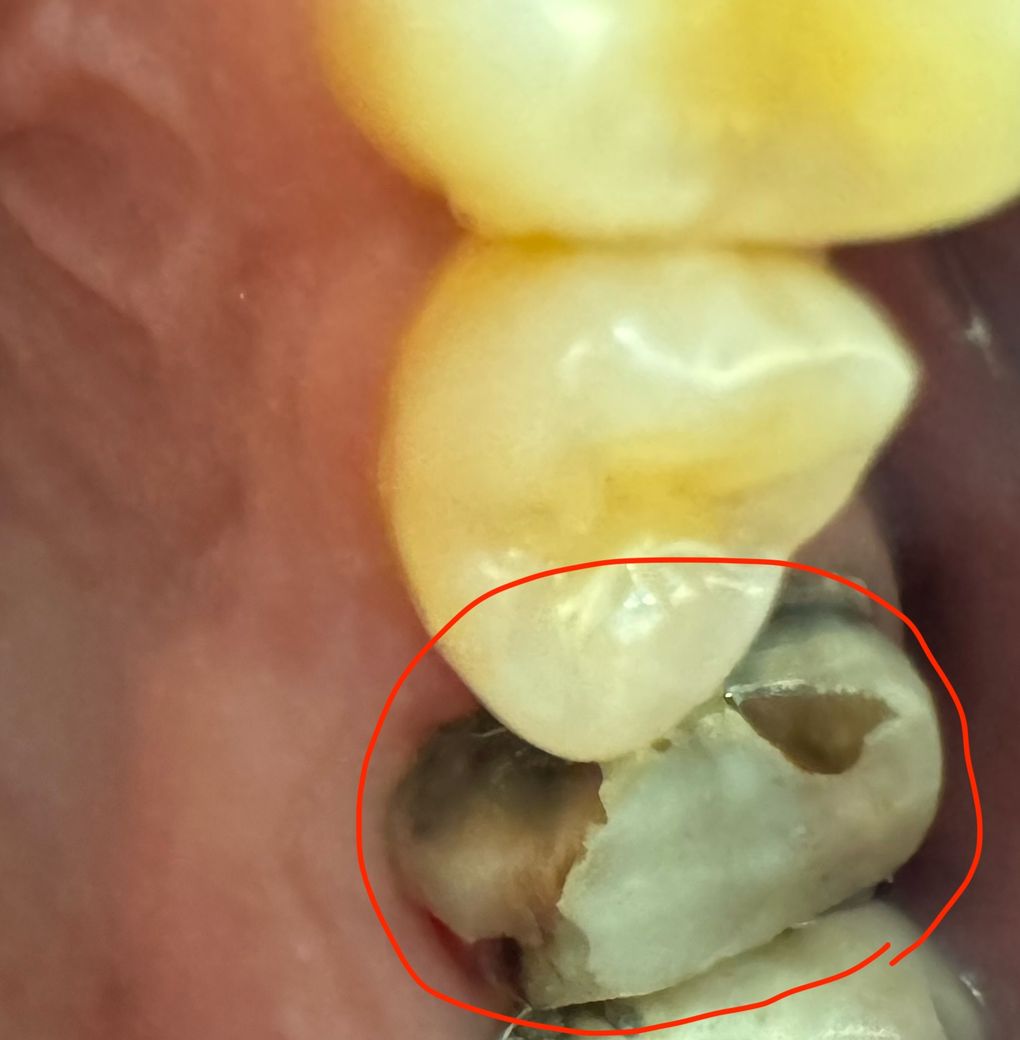

크라운이 떨어졌어요. 안 부분이 새까맣고 이가 깨져벼렸는데 임플란트 해야할까요?

크라운이 탈락되고 나니 치아 전체 부분이 까맣고

뭔가 바깥부분이 비어져있는거보아하니 약해서 깨진거같더라구요(추측)

사진상 이정도면 임플란트는 못 피할까요?

크라운이 탈락된 뒤 내부에 충치가 있다면 검은색으로 보일 수 있습니다. 크라운 내부에 충치가 있었다면 충치를 치료하고 보철 치료를 해야 할 수도 있습니다.

크라운이 떨어진 부위의 치아가 많이 약하고 파손이되는 경우에는 자연치아 보존이 어려울수 있으며, 이 경우에는 발치후에 임플란트 치료가 필요로 됩니다.

사진만으로는 판별하기가 어렵습니다. 치아가 전체적으로 푸석한 경우라면 임플란트 가능성은 높습니다.

신경치료 후 치아를 보강하는 코어가 떨어져 나간 것 같고 그건 다시 떼워주면 됩니다 다만 치아에 추가적으로 이차충치가 있어 그부분을 치료해줘야 합니다